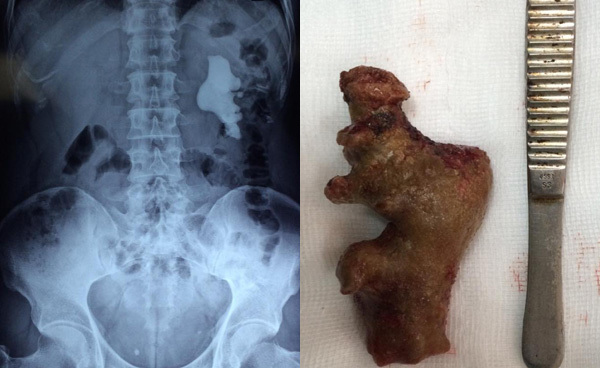

| Viên sỏi được lấy ra to như củ gừng, dài 11cm |

Theo bác sĩ Thảo, sau 2,5 tiếng phẫu thuật (bình thường chỉ mất 1 tiếng), khi lấy ra viên sỏi dài tới 11cm, to như củ gừng.